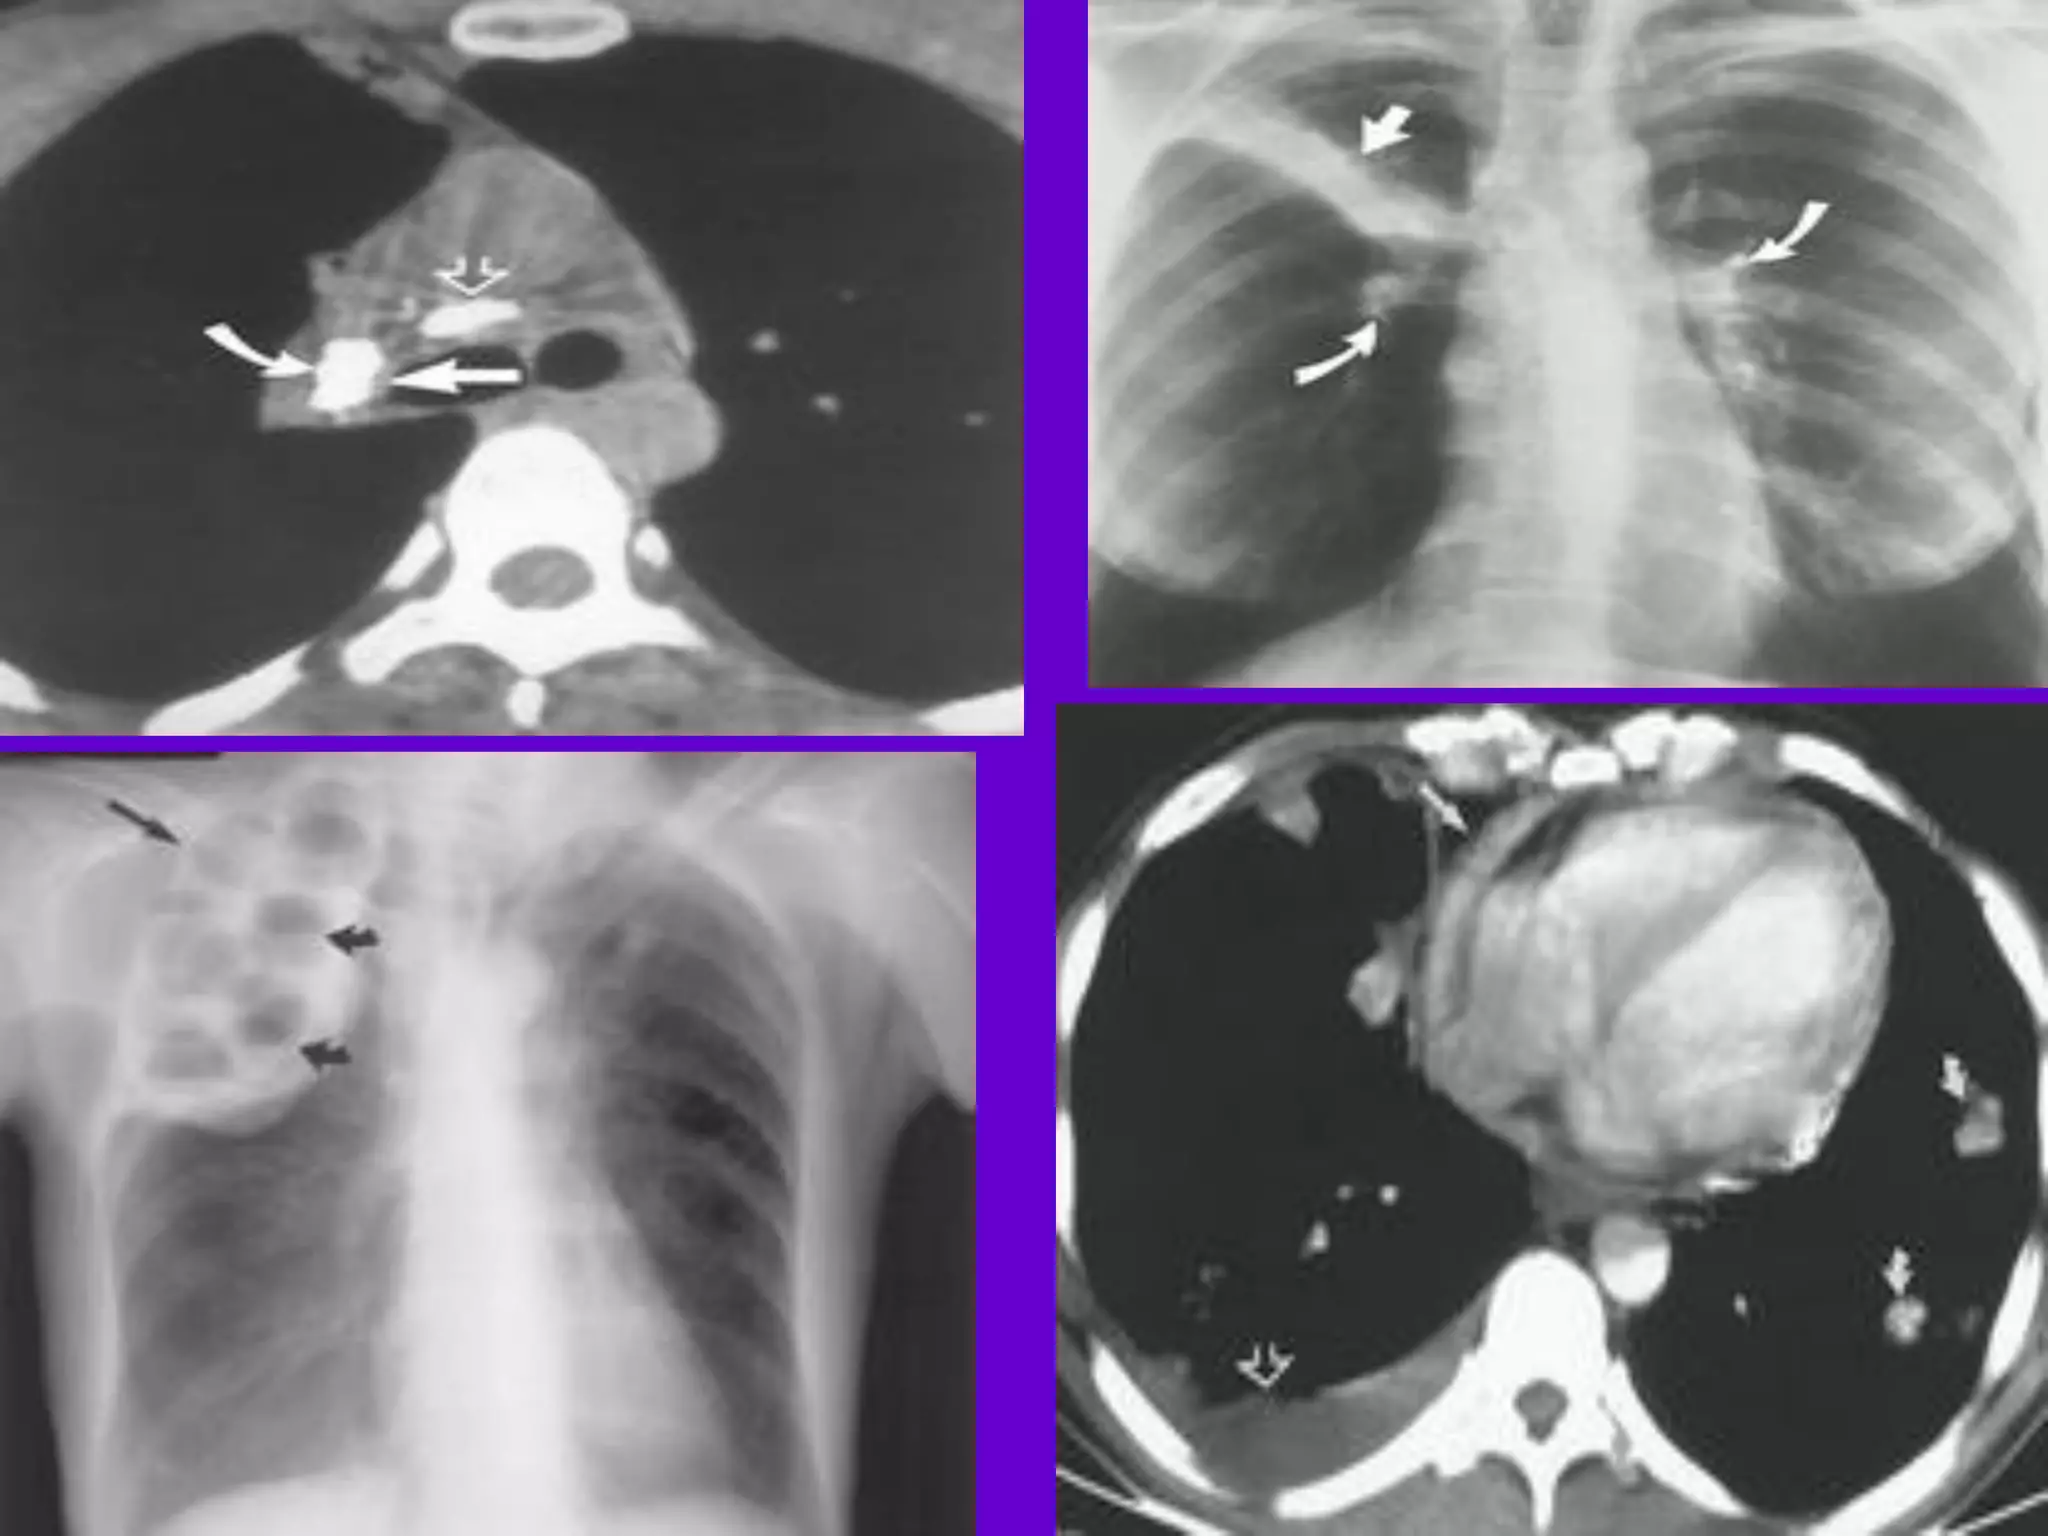

Pulmonary TB :

Lobar Pneumonia

􀂄

CT is superior than plain CXR in picking

up the

consolidation, atelectasis and the hilar LN

thereby

making the diagnosis easy.

􀂄 MRI reveals some of these changes,

however, CT is

the diagnostic modality of choice in such

cases.

Bronchopneumonia

On CT it is usually B/L and widespread,

not always

symmetrical involvement of lungs.

Hilar and Mediastinal

Lymphadenopathy

CT and MRI depict the hilar and

mediastinal LN

equally well.

􀂄 Calcification in the nodes is however

better seen on

CT.

􀂄 Necrosis is seen as focal areas of low

attenuation on

a CECT.

􀂄 On MRI focal necrosis is seen as areas

of increased

signal intensity on T2W images.

EBTB

HRCT is sensitive in the detection of

early

endobronchial spread of disease.

Miliary TB

􀂄 Earliest form of miliary TB is detectable

on HRCT.

􀂄 Coalescing nodules result into patchy

irregular

opacities and HRCT shows this variation

effectively

and has been described as “snowstorm

appearance”.

􀂄 HRCT shows cavitation, which is not

evident on plain

CXR.

Pleural Effusion 􀂄

􀂄 CT is sensitive to diagnose and define

even minimal

pleural effusion/pleural calcification.